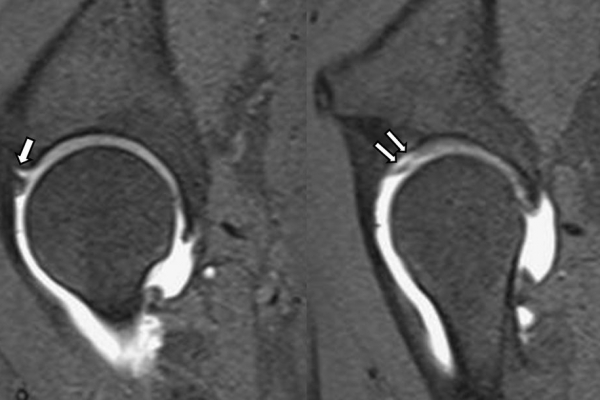

Είναι μια ελάχιστα επεμβατική απεικονιστική μέθοδος που επιτρέπει τη λεπτομερέστερη διερεύνηση του εσωτερικού των αρθρώσεων. Η ασφαλής έγχυση σκιαγραφικού εντός της άρθρωσης υπό ακτινολογική καθοδήγηση και η ακόλουθη απεικόνιση της άρθρωσης με αξονική ή μαγνητική τομογραφία (ή και με συνδυασμό των μεθόδων) αποσαφηνίζει βλάβες του χόνδρου και κακώσεις-ρήξεις συνδέσμων και τενόντων με υψηλή ακρίβεια, συμβάλλοντας σημαντικά στο λεπτομερή χειρουργικό σχεδιασμό.